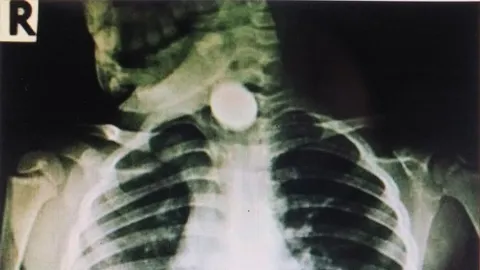

แม่เล่าอุทาหรณ์ ลูกชายอมเหรียญ 5 แล้วพลาดลงคอ เอกซเรย์พบอยู่ในหลอดอาหาร